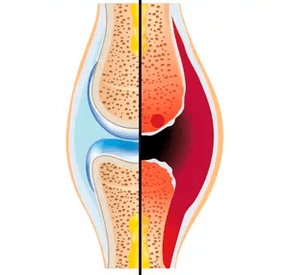

Vergleichende Merkmale von Arthritis und Arthrose

Um die Prinzipien der Erhaltung gesunder Gelenke zu verstehen, ist es notwendig, zwischen zwei Hauptpathologien zu unterscheiden – Arthritis und Arthrose. Trotz der Ähnlichkeit der Symptome (Schmerzen, eingeschränkte Beweglichkeit) sind diese Krankheiten unterschiedlicher Natur, was die Merkmale der Pflege und Prävention bestimmt.

| Essenz des Prozesses |

Entzündlich |

Degenerativ-dystrophisch |

| Primäres Ziel |

Synovialmembran, Gelenkkapsel |

Gelenkknorpel, subchondraler Knochen |

| Äußere Manifestationen |

Ödeme, Hyperämie, lokaler Temperaturanstieg |

Gelenkverformung aufgrund von Knochenwachstum |